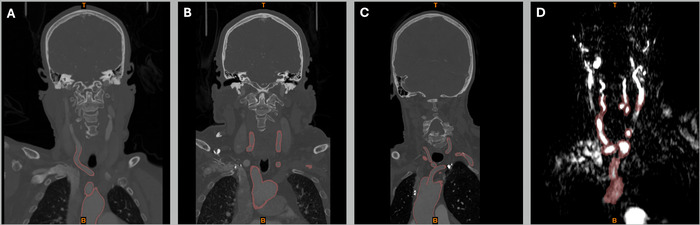

Methods: To better understand the challenges of tortuous anatomy, we fabricated 3D-printed models of the aortic arch and major branch vessels based on the imaging of 4 patients.

Results: These patient-specific models were realistic representations of the intricate vascular pathways and provided enhanced visualization of the complex vascular structures. The measured diameters of the 3D-fabricated models closely matched the values reported in the literature, confirming the physical accuracy of the models. Creating an individual anatomic model required an average of 4 hours of digital processing and 13.71 hours of 3D printing, with a materials cost of approximately $17.31.